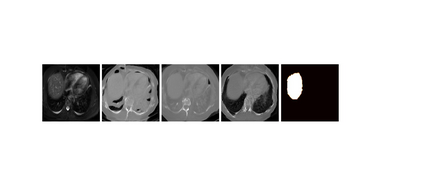

This work presents a novel framework CISFA (Contrastive Image synthesis and Self-supervised Feature Adaptation)that builds on image domain translation and unsupervised feature adaptation for cross-modality biomedical image segmentation. Different from existing works, we use a one-sided generative model and add a weighted patch-wise contrastive loss between sampled patches of the input image and the corresponding synthetic image, which serves as shape constraints. Moreover, we notice that the generated images and input images share similar structural information but are in different modalities. As such, we enforce contrastive losses on the generated images and the input images to train the encoder of a segmentation model to minimize the discrepancy between paired images in the learned embedding space. Compared with existing works that rely on adversarial learning for feature adaptation, such a method enables the encoder to learn domain-independent features in a more explicit way. We extensively evaluate our methods on segmentation tasks containing CT and MRI images for abdominal cavities and whole hearts. Experimental results show that the proposed framework not only outputs synthetic images with less distortion of organ shapes, but also outperforms state-of-the-art domain adaptation methods by a large margin.